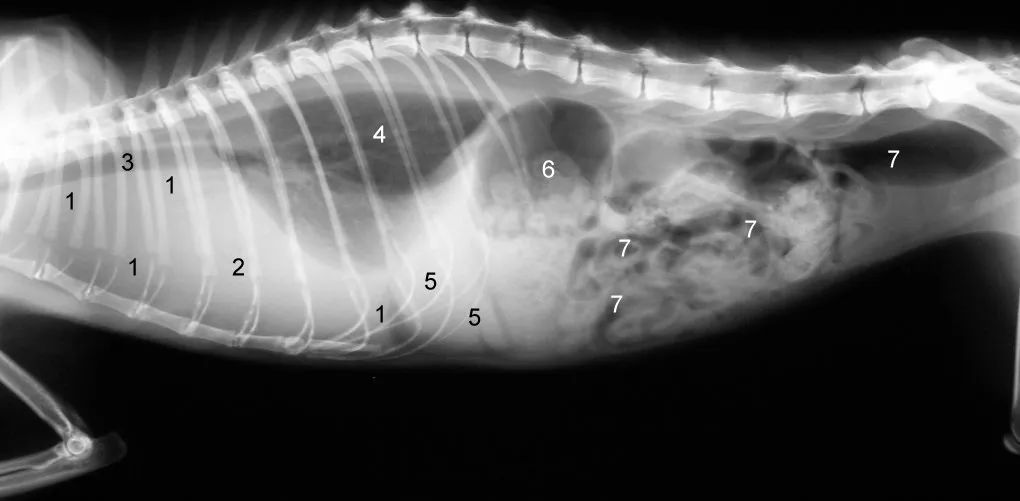

猫传腹猫咪的X光片:1因胸腔下部积液导致弥漫性阴影,2心脏因胸腔积液而无边界可见,3 气管,4肺(只有一小部分仍在通气),5肝脏, 6胃, 7肠